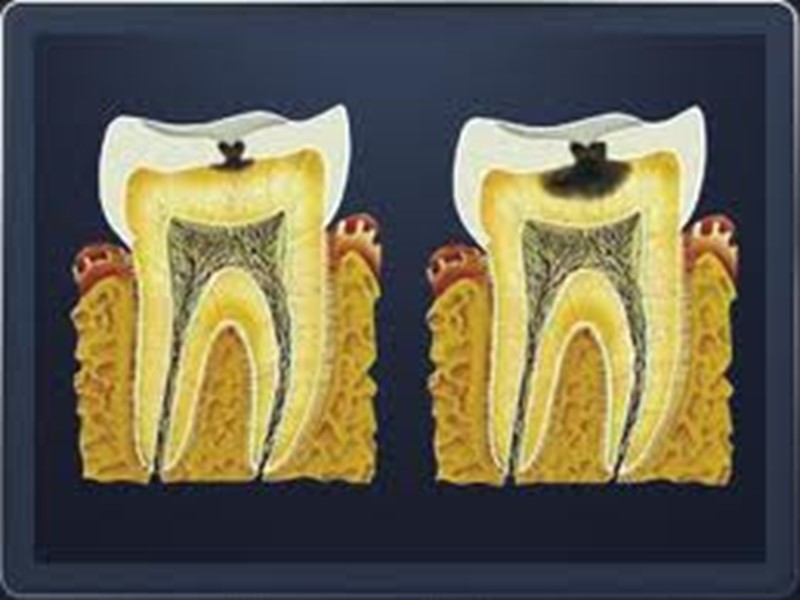

Классификация кариеса Начальный кариес (кариес в стадии пятна); Поверхностный кариес; Средний кариес; Глубокий кариес.

Дифференциальная диагностика среднего кариеса Средний кариес дифференцируют с: 1. поверхностным кариесом; 2. глубоким кариесом; 3. клиновидным дефектом; 4. эрозией твердых тканей; 5. некрозом твердых тканей зуба; 6. хроническим периодонтитом.

Дифференциальная диагностика поверхностного, среднего и глубокого кариеса Общее: 1. жалобы на боли от раздражителей, быстропроходящие после их устранения; 2. причина возникновения - зубная бляшка, локальное снижение рН; 3. возникает после прорезывания, содержание фтора в питьевой воде меньше 0,8-1 мг/л; 4. поражаются молочные и постоянные зубы; 5. прогрессирует, осложняется пульпитом и периодонтитом; 6. локализация, характерная для кариеса; 7. кариозная полость не сообщается с полостью зуба; 8. перкуссия безболезненна; 9. термодиагностика: возникает быстропроходящая боль на температурный раздражитель; 10. на рентгенограмме: кариозная полость не сообщается с полостью зуба, в периапикальных тканях изменений нет.